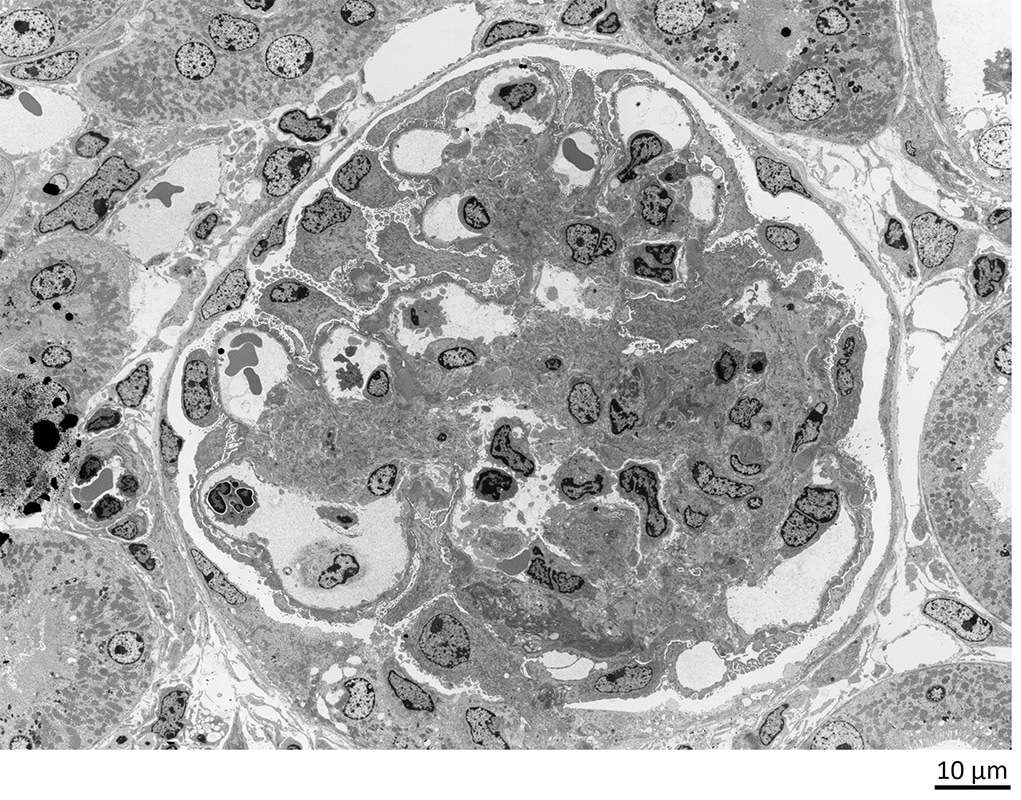

病理組織解析の事例では、腎臓疾患があります。腎臓は構造が複雑で、病状が悪化するまで自覚症状が現れにくく、疾患の分類が難しいといった理由から「わかりにくい病気」とされてきました。

基本的にはTEM観察により腎糸球体への沈着物や基底膜など構造の微細な変化をとらえることで、病気を診断することができます。

TEMによるラットの腎臓の観察例